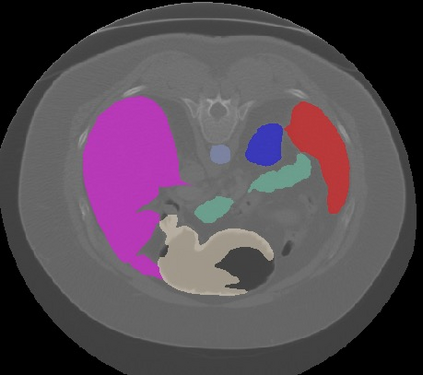

Transformers, the default model of choices in natural language processing, have drawn scant attention from the medical imaging community. Given the ability to exploit long-term dependencies, transformers are promising to help atypical convolutional neural networks (convnets) to overcome its inherent shortcomings of spatial inductive bias. However, most of recently proposed transformer-based segmentation approaches simply treated transformers as assisted modules to help encode global context into convolutional representations without investigating how to optimally combine self-attention (i.e., the core of transformers) with convolution. To address this issue, in this paper, we introduce nnFormer (i.e., Not-aNother transFormer), a powerful segmentation model with an interleaved architecture based on empirical combination of self-attention and convolution. In practice, nnFormer learns volumetric representations from 3D local volumes. Compared to the naive voxel-level self-attention implementation, such volume-based operations help to reduce the computational complexity by approximate 98% and 99.5% on Synapse and ACDC datasets, respectively. In comparison to prior-art network configurations, nnFormer achieves tremendous improvements over previous transformer-based methods on two commonly used datasets Synapse and ACDC. For instance, nnFormer outperforms Swin-UNet by over 7 percents on Synapse. Even when compared to nnUNet, currently the best performing fully-convolutional medical segmentation network, nnFormer still provides slightly better performance on Synapse and ACDC.